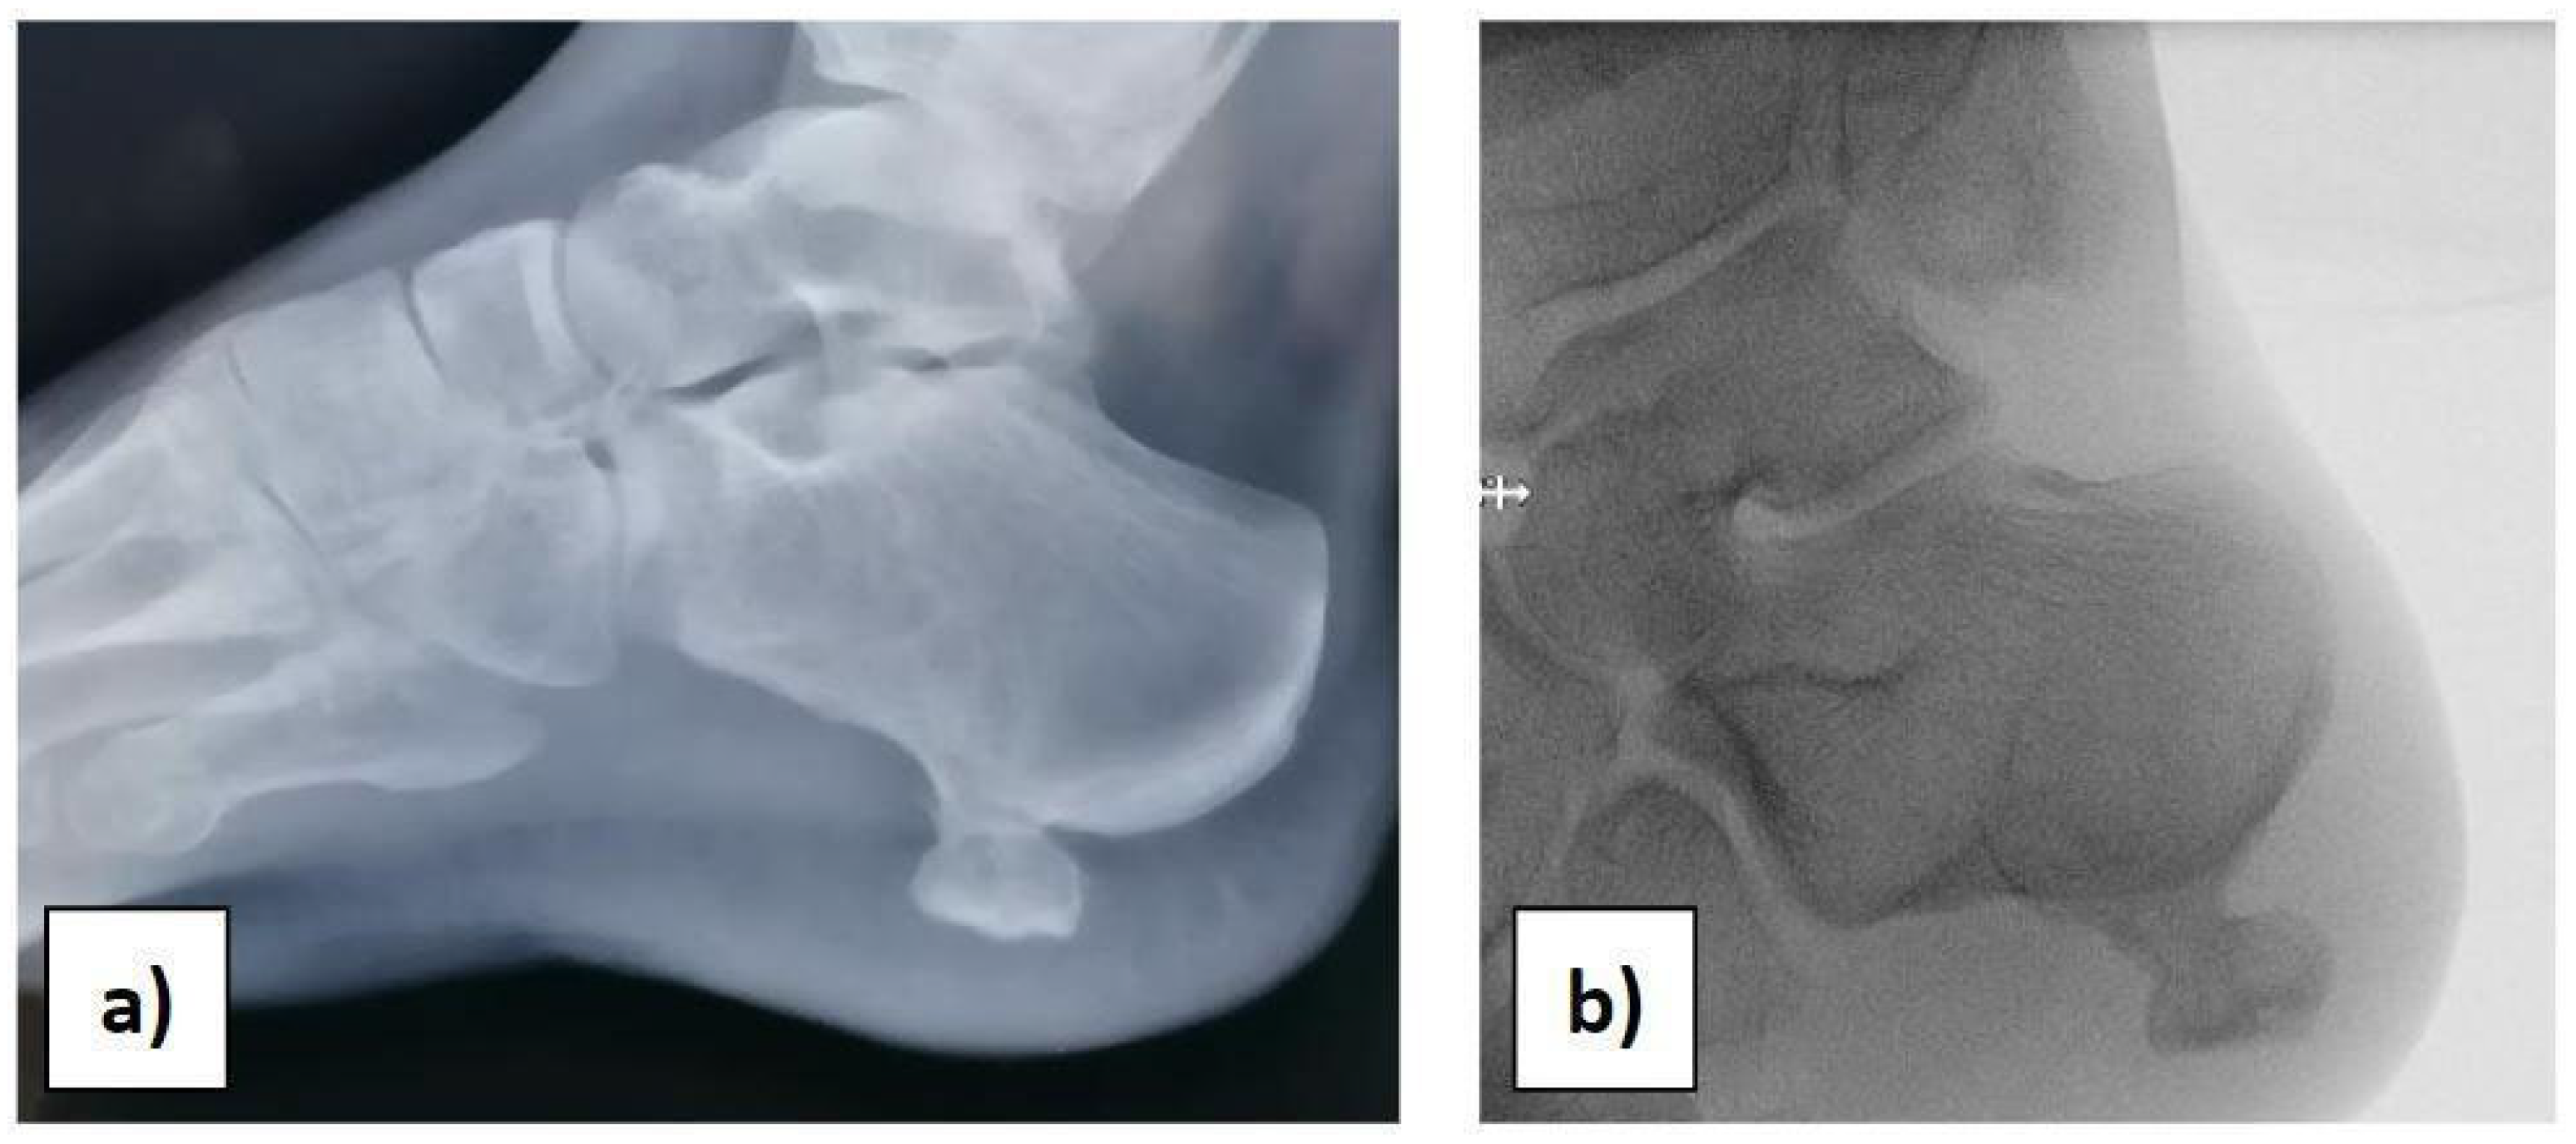

2. Clinical Case